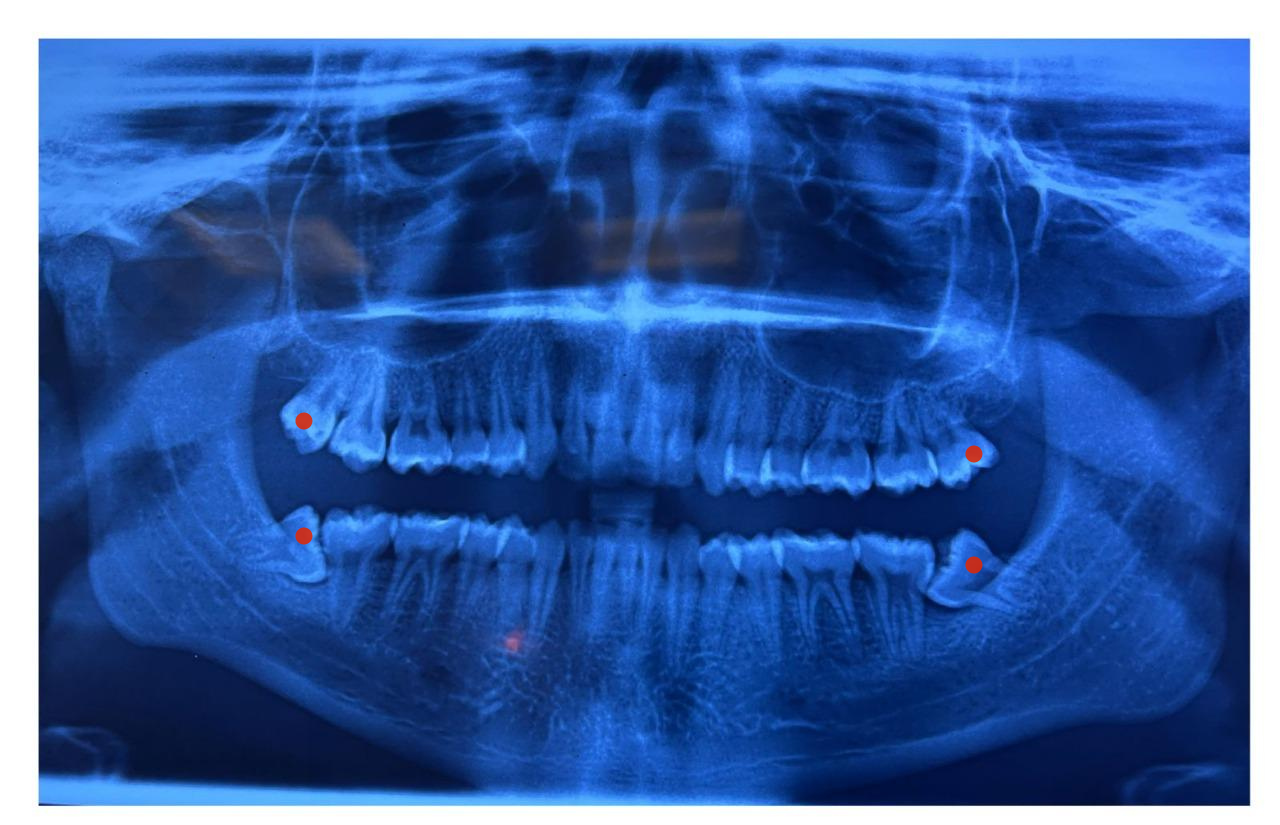

Wisdom Teeth Removal

Adults typically have 32 teeth. Of these, wisdom teeth, or third molars, are the last to appear. They appear at the end of the upper and lower gums, right in the back of the mouth.

Most of the time wisdom tooth does not erupt in the right direction and becomes impacted.

An impacted wisdom tooth can cause a range of problems. These include: